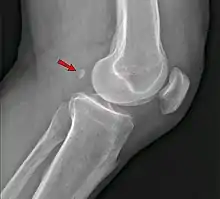

Radiographie de profil du genou montrant la fabella en arrière du plan des condyles fémoraux.

La fabella est située dans le tendon du chef latéral du muscle gastrocnémien et apparaît entourée sur son versant antérieur comme postérieur par les fibres tendineuses sur les études histologiques[3]. Elle est reliée dans la plupart des cas à la tête de la fibula par un ligament fabello-fibulaire[3]. Sa taille est variable, comprise entre 4 et 13 mm[3].